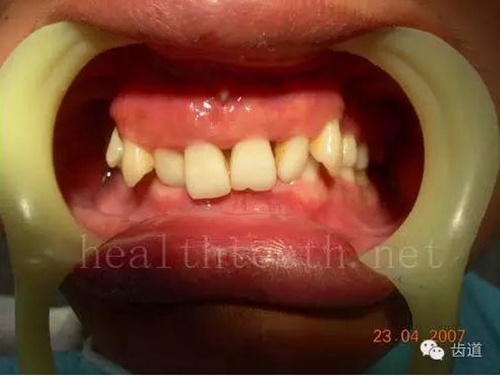

九、關(guān)于智齒(第八顆牙)

四顆長(zhǎng)不出來的智齒

80.jpg